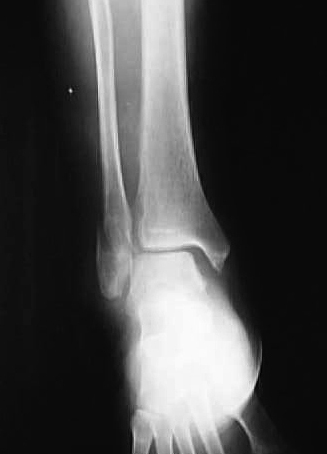

正面像において腓骨下端部の骨折が認められ、中枢骨片の内側への転位が認められた。側面像において中枢骨片は前下方、末梢骨片は外後上方の骨片への転位が認められた(図1、2)。

図1

図2